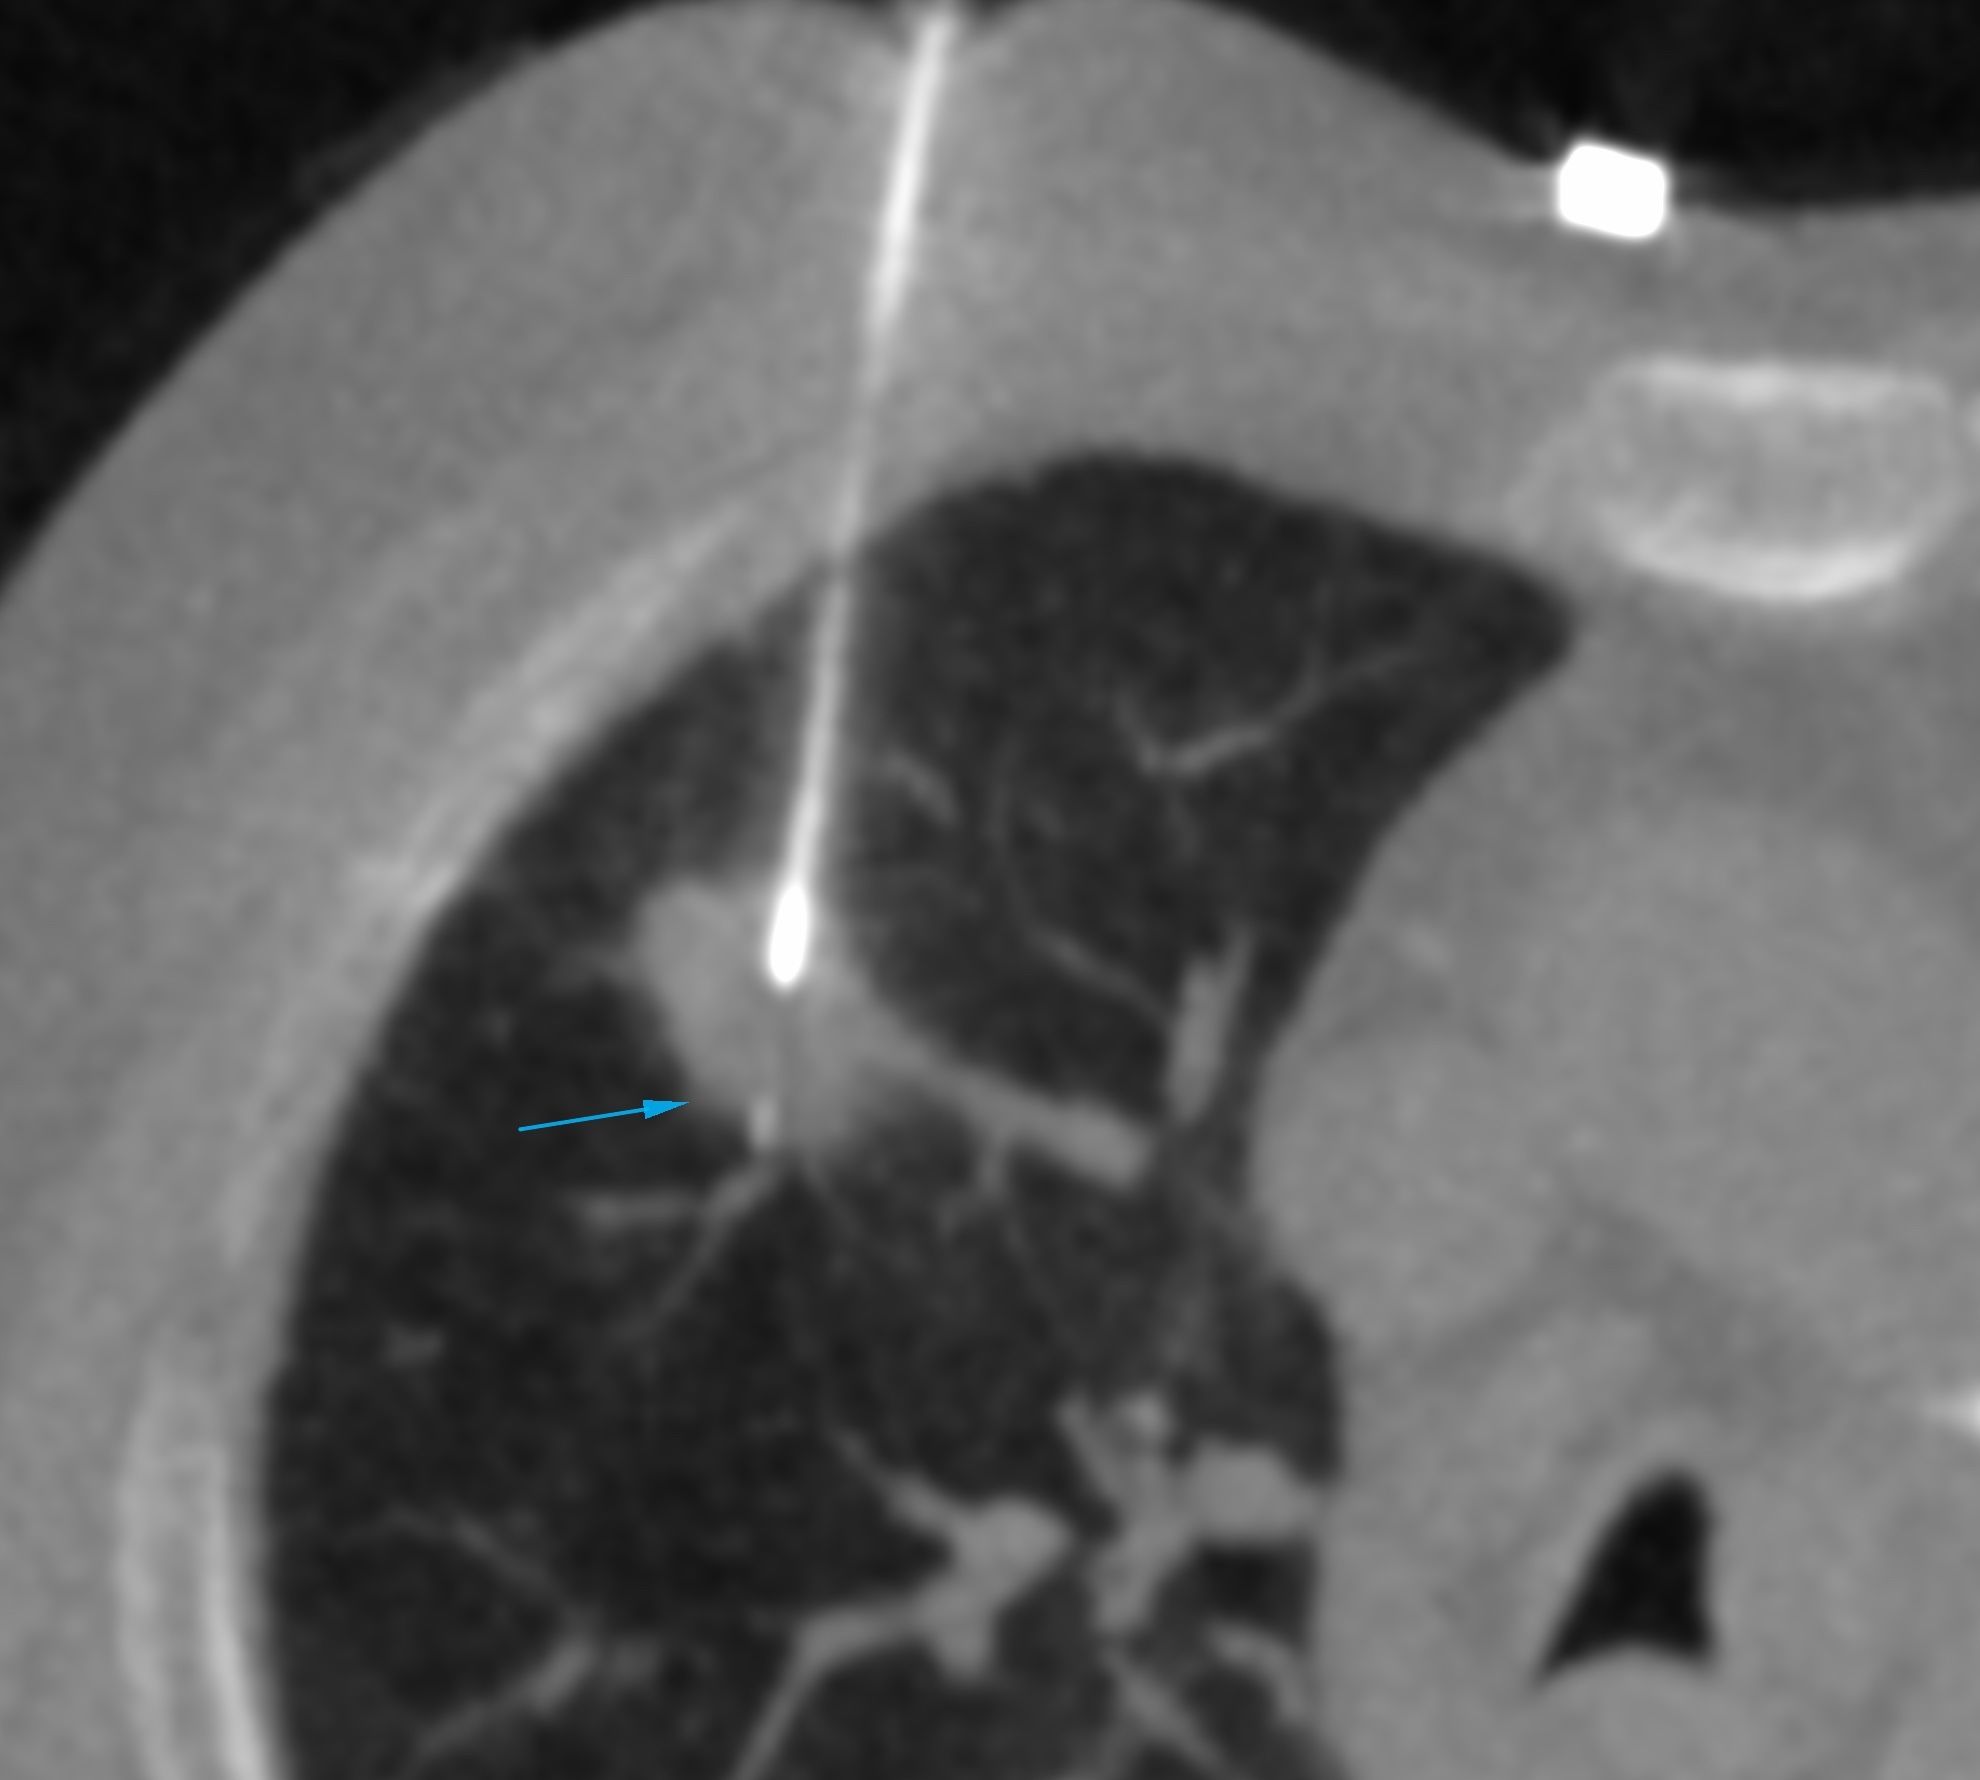

A 67-years old ex-smoker came for a CT-guided biopsy. The biopsy was uneventful.

Lesion Biopsied: Lung nodule

Size of Lesion: 15.8 mm z axis x 17.6 mm

Gun: 20 G 10 mm throw

No of cores: 5 for histopath and 3 for micro

Diagnosis: Poorly differentiated adenosquamous carcinoma